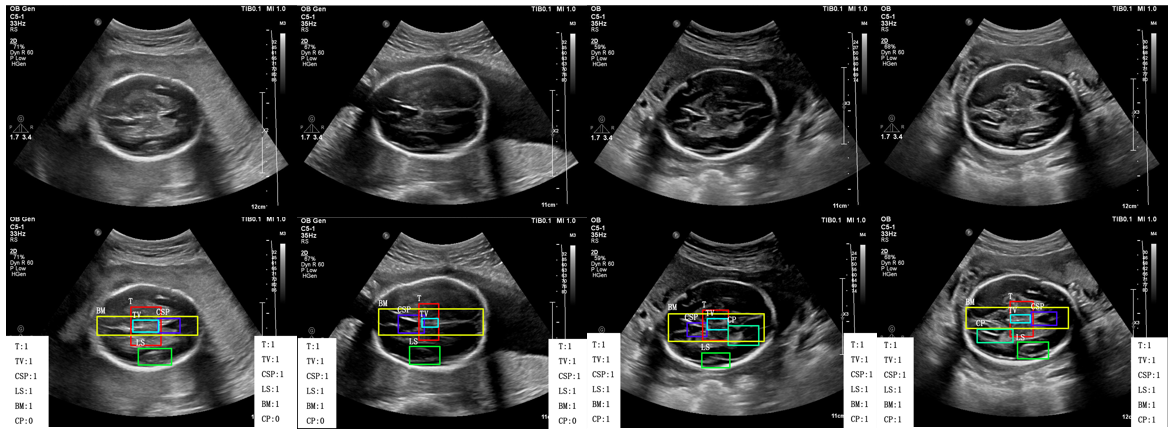

There are various types of challenges concerning the automatic quality control of FS images. As illustrated in Fig. 2, the main challenges can be divided into three types: the first type is that the image usually suffers from the influence of noise and shadowing effect, the second type is that similar anatomical structures could be confused due to the low resolution of the images and the third type is that the fetal location during the scanning is unstable which will cause the rotation of some anatomical structure. The first type of challenges can only be solved by using more advanced scanning machines, but we can tackle the rest two challenges by a more scientific approach. Specifically, we need to find an efficient feature extraction method, which remains robust to the distinction between image rotation and similar structures. In recent years, deep learning techniques have been widely applied in many medical imaging fields due to the technique’s stability and efficiency, such as anatomical object detection and segmentation [11, 36, 10] and brain abnormalities detection [17, 32]. A well-designed neural network can efficiently extract the features for classification and identification. In our approach, we firstly design a Feature Extraction Network (FEN) to extract deep level features from FS images, then we feed the extracted features to the region proposal network (RPN) and then to class prediction network (CPN) to identify the region of interest (ROI) and classification simultaneously. Besides, to further improve the performance of our framework, we introduce a relation module to fully utilize the relationship between the entire image and each detected structure. In conclusion, our contribution can be summarized as follows:

Fig. 7, Fig. 8 and Fig. 9 depict the comparison of our results with the manually labeled images by experts in the head section, abdominal section, and heart section, respectively. Our method displays the classification and detection results simultaneously to assist in sonographers’ observation. It can be seen that our method is perfectly aligned with professional sonographers.